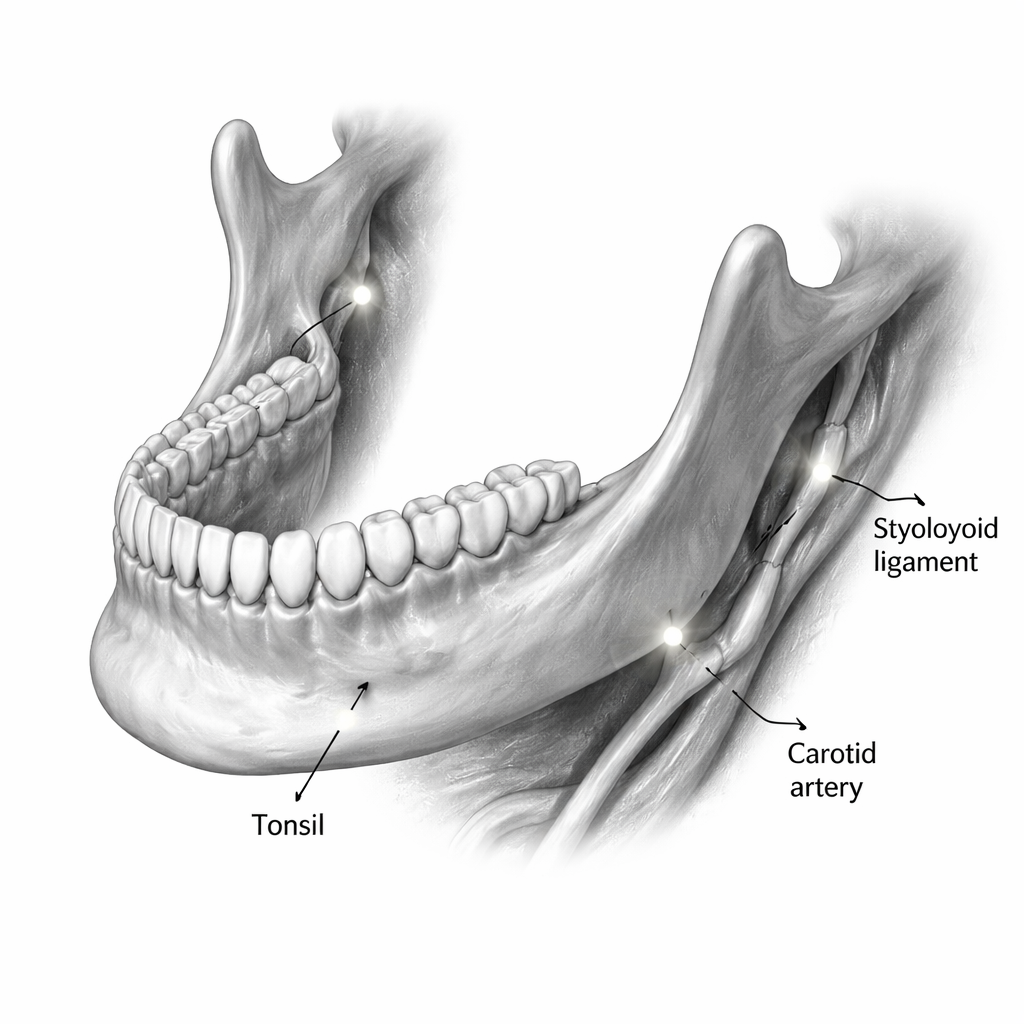

Il team ha riesaminato 420 scansioni CBCT eseguite tra il 2020 e il 2024 in una clinica odontoiatrica universitaria in Iran. Ogni scansione copriva o la mascella superiore o la mandibola utilizzando un campo visivo standardizzato. I pazienti avevano un’età compresa tra 6 e 82 anni. Sono state escluse le scansioni di scarsa qualità e quelle distorte da interventi chirurgici o da rare patologie calcificanti. Due radiologi esperti, addestrati in precedenza su casi di esempio, hanno controllato indipendentemente ogni scansione per tipi specifici di calcificazioni dei tessuti molli, come i tonsilloliti, i legamenti stiloiodei calcificati, i calcoli salivari, i linfonodi calcificati e, nelle scansioni della mandibola, depositi calcificati nelle arterie carotidi del collo. Hanno misurato la dimensione maggiore di ogni reperto e li hanno raggruppati come piccoli (1 millimetro o meno), medi (1–3 millimetri) o grandi (3 millimetri o più). L'accordo tra i lettori è stato quasi perfetto, il che significa che i reperti erano altamente affidabili.

Le calcificazioni dei tessuti molli erano comuni. Complessivamente, erano circa 1,3 volte più probabili nelle scansioni focalizzate sulla mandibola rispetto a quelle mirate alla mascella. In entrambe le regioni, i tonsilloliti erano il tipo più frequente, seguiti dai legamenti stiloiodei calcificati. Nelle scansioni della mandibola, circa un paziente su tre presentava tonsilloliti, mentre nelle scansioni della mascella quasi uno su cinque li aveva. La maggior parte dei depositi, inclusi i tonsilloliti e i legamenti calcificati, rientrava nella categoria di dimensione “media”, abbastanza grandi da essere chiaramente visibili sulla CBCT ma spesso ancora inosservati nella vita quotidiana.

L’età è risultata essere un forte predittore. Con l’avanzare dell’età, le calcificazioni non solo comparivano più frequentemente ma tendevano anche a essere più grandi. Le persone sopra i 50 anni avevano più del doppio delle probabilità di avere tonsilloliti ed erano molto più propense a mostrare placche calcificate nell’area carotidea nelle scansioni della mandibola. Nelle scansioni della mascella, grandi legamenti calcificati erano molto più comuni dopo i primi quarant’anni. Sono emersi anche alcuni schemi legati al sesso: nel campo della mascella, le donne mostravano più spesso legamenti stiloiodei calcificati, mentre negli uomini erano più frequenti calcificazioni a livello cutaneo. Tuttavia, molti tipi di calcificazione erano troppo rari per trarre conclusioni solide sulle differenze legate al sesso. Gli autori sottolineano che le scansioni della mandibola, in particolare, catturano regioni vicine alla gola e ai vasi del collo, rendendole particolarmente preziose per individuare tonsilloliti e possibili calcificazioni arteriose.